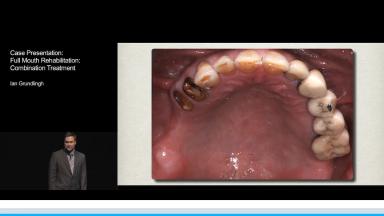

Case Presentation: Full Mouth Rehabilitation - Combination Treatment

Andries Adam Grundlingh

The rehabilitation of a partially dentate patient with a skeletal and dentate Class III relationship remains a challenge. The concerns raised by this patient were aesthetics and loss of function. He had a history of chronic sinusitis and was smoking at least ten cigarettes per day. The intra oral examination revealed loss of posterior teeth due to caries, which resulted in severe bone loss, loss of occlusal vertical dimension and compromising the anterior aesthetics.